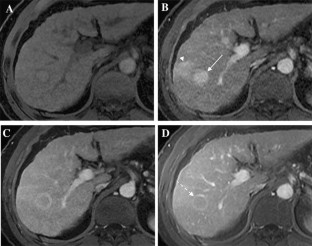

The Liver Imaging Reporting and Data System (LI-RADS) was designed to standardize the interpretation and reporting of observations seen on studies performed in patients at risk for development of hepatocellular carcinoma (HCC). The LI-RADS algorithm guides radiologists through the process of categorizing observations on a spectrum from definitely benign to definitely HCC. Major features are the imaging features used to categorize observations as LI-RADS 3 (intermediate probability of malignancy), LIRADS 4 (probably HCC), and LI-RADS 5 (definite HCC). Major features include arterial phase hyperenhancement, washout appearance, enhancing capsule appearance, size, and threshold growth. Observations that have few major criteria are assigned lower categories than those that have several, with the goal of preserving high specificity for the LR-5 category of Definite HCC. The goal of this paper is to discuss LI-RADS major features, including definitions, rationale for selection as major features, and imaging examples.

Fig. 2